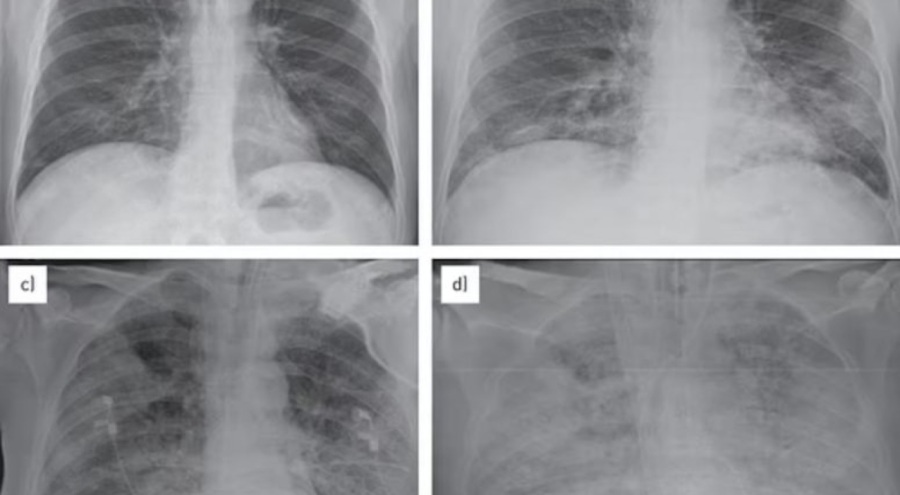

Bilim insanları bu duruma "beyaz akciğer zatürre salgını" adını verirken bunun sebebi olarak da röntgende hastaların ciğerlerinin beyaz renkte opaklaşması gösterildi. ABD'nin önde gelen medya kuruluşlarından Bloomberg de Çin'de antibiyotik kullanımının çok yoğun olduğunu ve bazı doktorların grip ve soğuk algınlığında bile ilk olarka antibiyotikleri kullandığını yazdı.